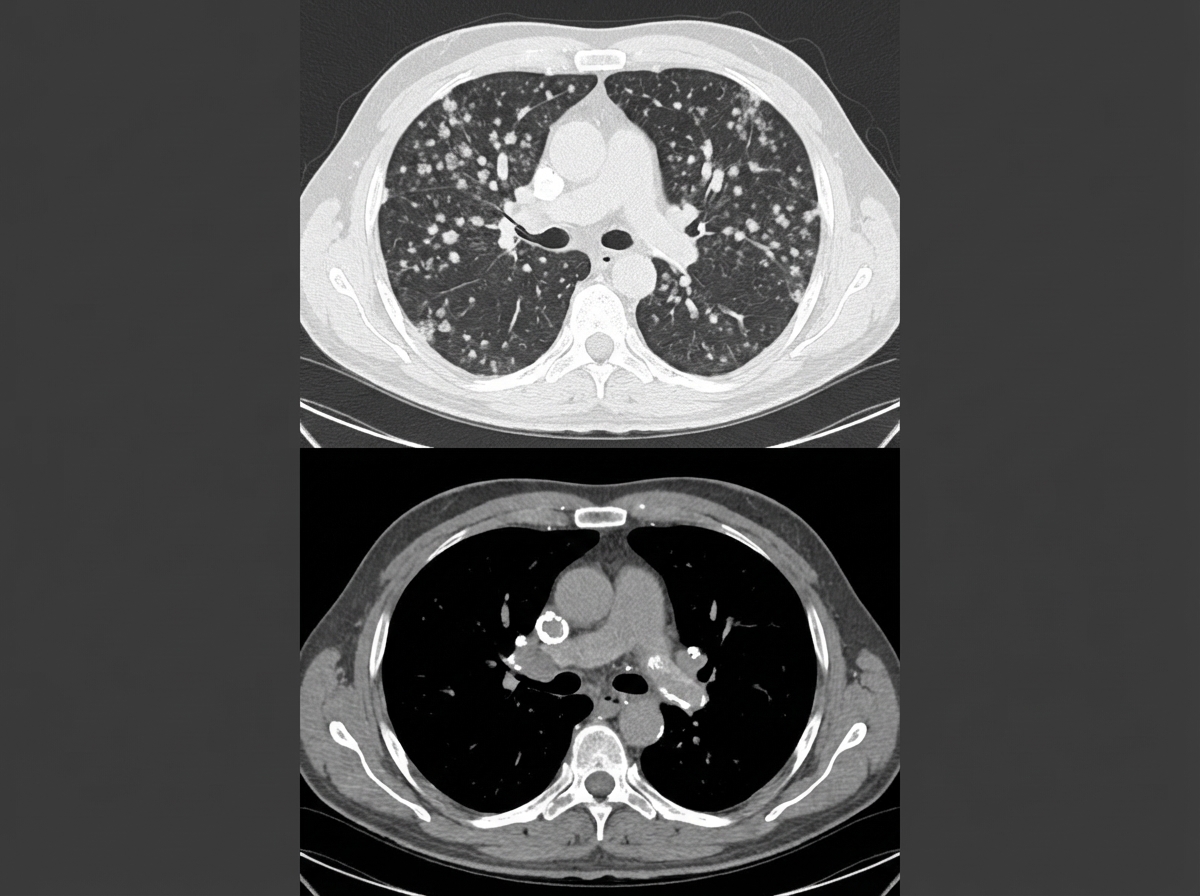

The following CT chest shows the presence of?

Explanation: ***Pneumoconiosis*** - CT chest shows **bilateral small nodular opacities** with **upper lobe predominance**, characteristic of pneumoconiosis from occupational dust exposure. - May progress to **progressive massive fibrosis (PMF)** and show **eggshell calcification** of hilar lymph nodes, pathognomonic for silicosis. *Primary carcinoma of lung* - Typically presents as a **solitary pulmonary nodule** or **mass lesion** rather than bilateral small nodules. - Shows **irregular margins**, **spiculation**, and may have **pleural effusion** or **mediastinal lymphadenopathy**. *Bronchiectasis* - CT demonstrates **bronchial wall thickening** and **bronchial dilatation** with the classic **"tram-track" sign**. - Shows **"signet ring" appearance** where dilated bronchi appear larger than accompanying pulmonary arteries. *Chronic bronchitis* - CT findings include **bronchial wall thickening** and **peribronchial cuffing** without the nodular pattern seen here. - May show **mosaic attenuation** and **air trapping** on expiratory images, but lacks bilateral small nodules.